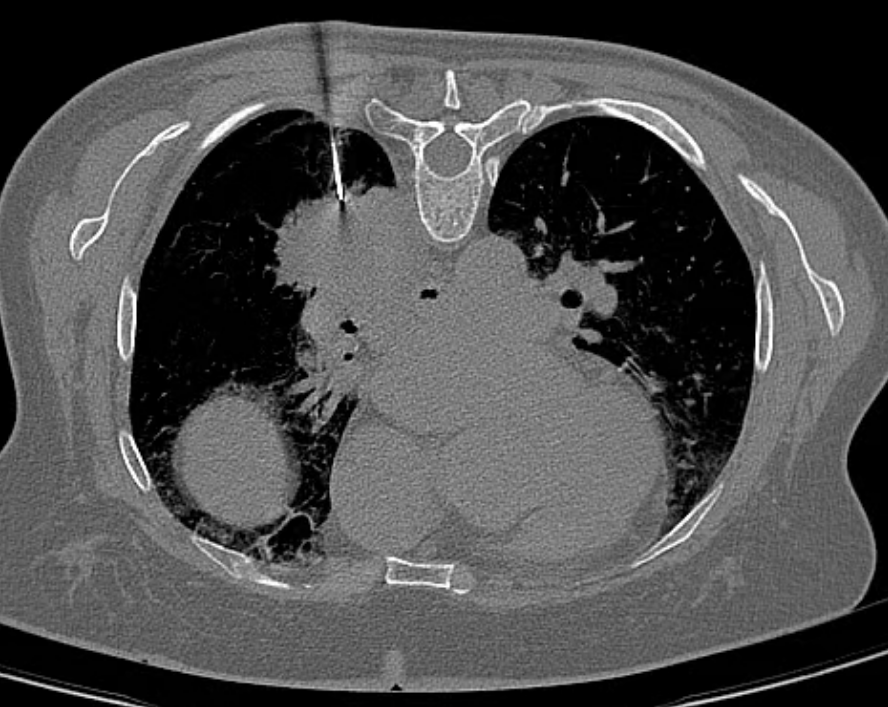

行肺穿刺活检术的是一位64岁的女性患者,两月前于当地医院行结核筛查发现结果异常,进一步行肺CT平扫发现右侧肺门占位性病变,增强扫描提示右侧肺门中央型肺癌,伴肺门淋巴结肿大,随后患者两次行支气管镜检查,结果均未见恶性细胞,仅见炎性细胞浸润,当地按结核治疗一段时间。2024年7月16日入我院行PET-CT检查提示右肺下叶背段软组织肿块,考虑恶性病变,结核不除外。肿瘤科专家团队邀请医学影像科CT介入团队进行深入讨论和综合评估后,决定行CT引导下的经皮肺穿刺活检术以明确诊断。征得患者及家属的知情同意并签字后,医学影像科CT介入团队仅使用10分钟即完成手术,术中取得3条组织后送病理,术后患者无不适,安全返回病房。几天后病理结果显示浸润性粘液腺癌。

CT引导下肺穿刺活检术是指通过CT扫描定位技术,实现了对肺部病灶的精确穿刺,获取病理样本。这一技术极大地提高了诊断的准确率,有效降低了误诊的风险。相较于传统手术,CT引导下的穿刺活检术具有创伤小、恢复快、安全性高的特点,显著降低了手术创伤,缩短了患者恢复时间,为肺部疾病的早期诊断和治疗提供了强有力的支持。